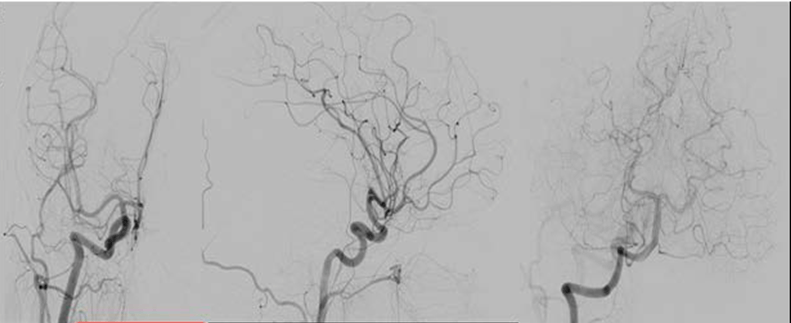

Consequently, a digital subtraction angiography (DSA) from the femoral artery was performed which did not reveal underlying vascular abnormalities (Figure 4).

Figure 4: Digital subtraction angiography imaging, revealing no pathological findings.